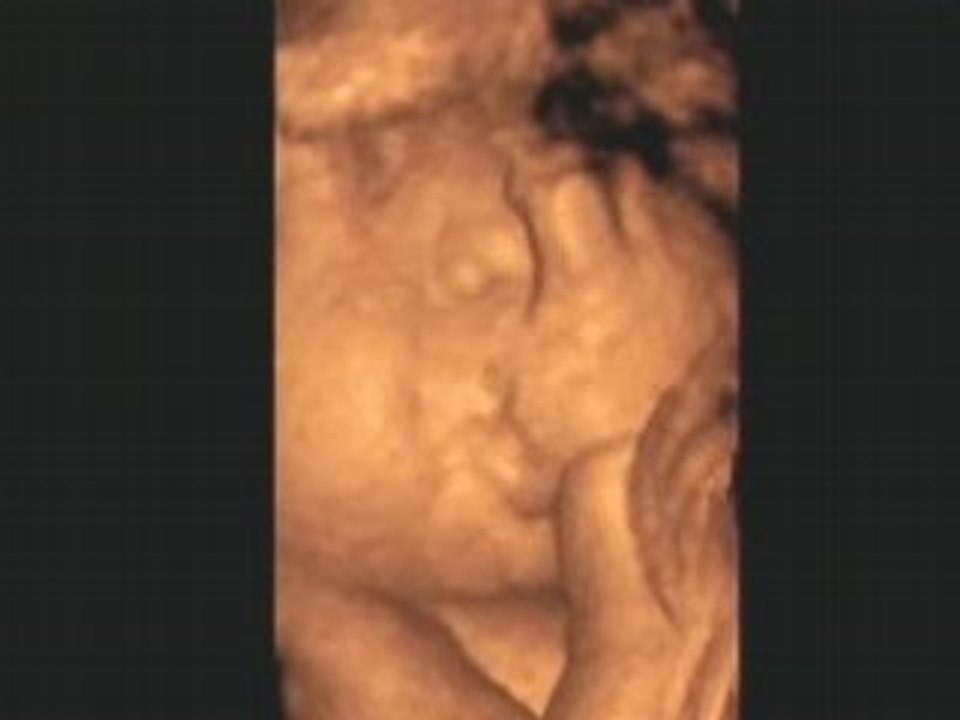

Le Monde selon Bébé Pour la fête des mères, un hommage sous forme de film Occasion de présenter aussi, et différemment, mon travail dans l'audiovisuel Le Monde selon Bébé est un documentaire en deux parties ( in utero et juste après la naissance) centré sur les perceptions du bébé Ce fut un travail intense et passionnant que deLe monde selon bébé FRENCH DVDRiP Durée 1h 23 min Date de sortie 13 XploraQuandLeCielSeDechaineDOCFRENCHHDTVXviDJSTS Genre Documentaire Durée 2 Heure 10 Minutes Date de sortie 2 février 13 Aujourd'hui, Mac Lesggy s'intéresse au temps qu'il fait !Le monde selon bébé un monde de sensations De Bernard George • France 05 0h42 • Documentaire / Santé et bienêtre À partir du septième mois de la grossesse, les cinq sens du bébé in utero deviennent fonctionnels Dans l'univers clos qui est le sien commence alors une formidable exploration sensorielle